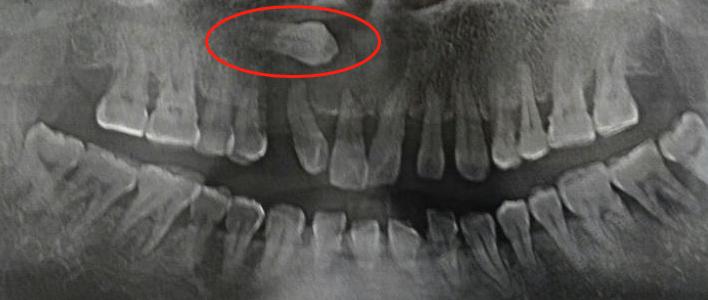

“医生,我这牙片怎么和别人的长得不一样呀?牙齿怎么长在上面的?”。

和普通牙片相比,上面这张牙片确实奇怪,这到底是怎么回事?会不会有什么影响?今天科普君就来和大家谈谈关于这颗“不正常的”牙齿是怎么回事?

像图片上的牙齿长出来以后埋伏在颌骨内,肉眼看不到牙齿的情况,一般称之为埋伏牙。